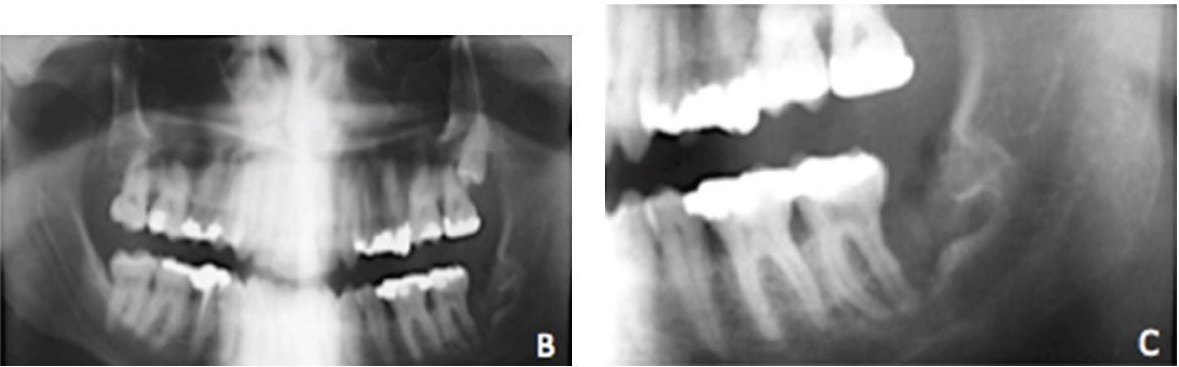

Если около корня образовалась капсула с жидкостью, это радикулярная киста зуба. Пациент с такой патологией может не предъявлять никаких жалоб. Неприятные ощущения возникают при нагноении содержимого полости или ее прорастании в гайморову пазуху. Долгое существование радикулярной кисты приводит к деформированию костной ткани и увеличению риска перелома челюсти.

Эта разновидность кистозных заболеваний является самой распространенной в стоматологии. Причем, на верхней челюсти новообразования появляются чаще, чем на нижней. А основная причина развития патологии – наличие инфекции. Формирование капсулы из соединительной ткани – ответная реакция организма, пытающегося изолировать очаг воспаления.

В большинстве случаев радикулярные кисты зуба появляются у пациентов с запущенным кариесом, пульпитом, периодонтитом, а также после неграмотного стоматологического вмешательства. Воспалительный процесс может начаться и в результате травмы зуба, при снижении иммунитета, после перенесенного инфекционного заболевания. Кистозные полости иногда вырастают при осложненном прорезывании зубов мудрости или неправильном прикусе.